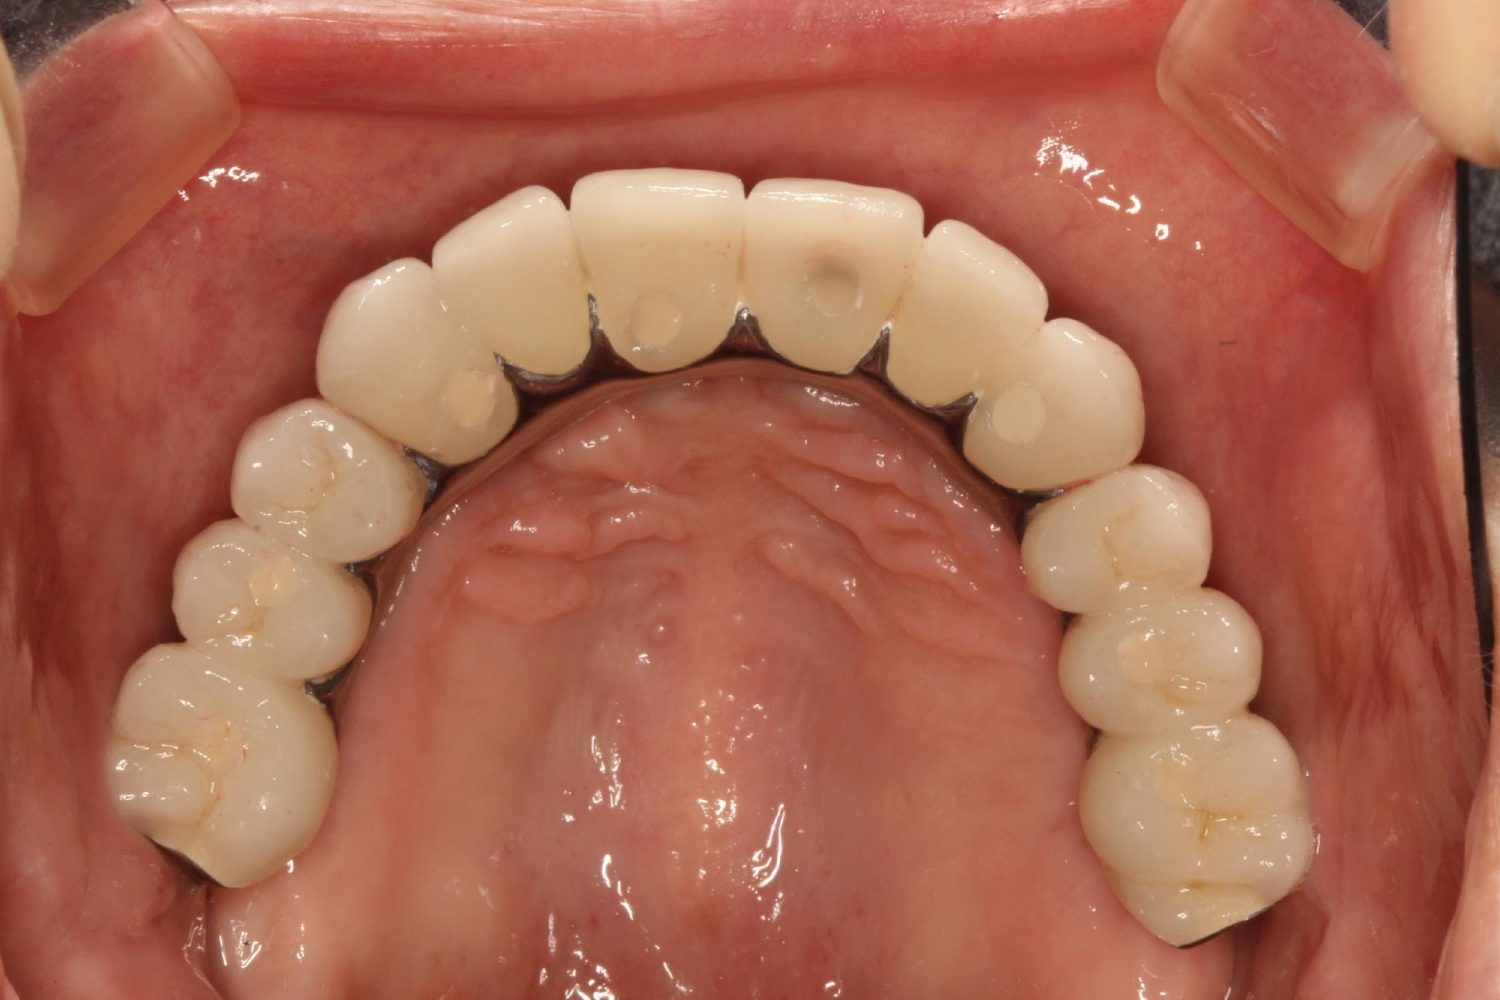

インプラント治療の症例紹介⑤

Before

After

主訴

歯肉腫脹、咬めるようにしたい

治療内容

重度歯周病により全ての残存歯保存不可能な状態。上下顎ボーンアンカードブリッジによる咬合再構成。

治療費

12,621,400円(税込)

治療期間

22ヶ月

通院回数

28回

想定されたリスク

※上部構造の形態が複雑になるため清掃が難しくなる、インプラント周囲炎の恐れがありました。

濱 仁隆先生

浜歯科

上顎8本下顎7本のインプラント体埋入によるボーンアンカードブリッジ。